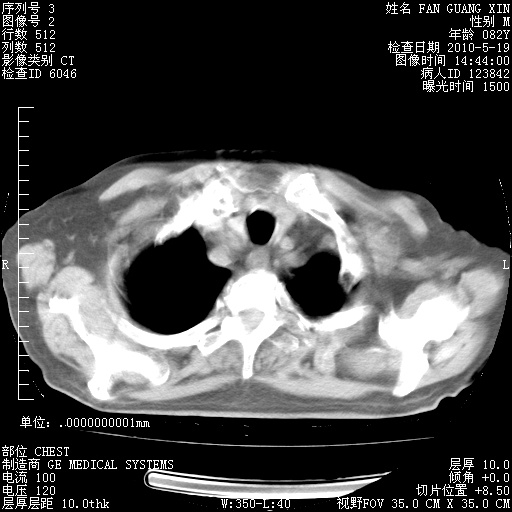

可改为口服强的松40-50mg/d治疗,若病情仍稳定,胸部阴影不再吸收可逐渐减量